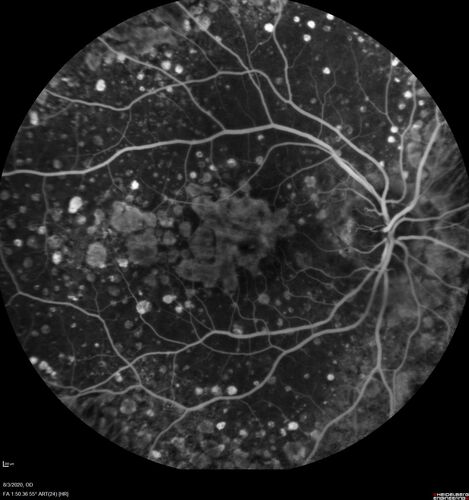

Age-related macular degeneration - Geographic Atrophy - Intermittent CME left eye from CRVO, Anemia, Diabetes

79 year old female - 3 years post CRVO in the left eye (20/32 VA) with intermittent CME.  Left eye is the better eye.  Vision is stable since 2 years ago

PMHx: Type II DM x 20 years, Chronic Anemia, Hyperlipidemia

VA 20/200 OD, 20/50 OS (usually 20/40)